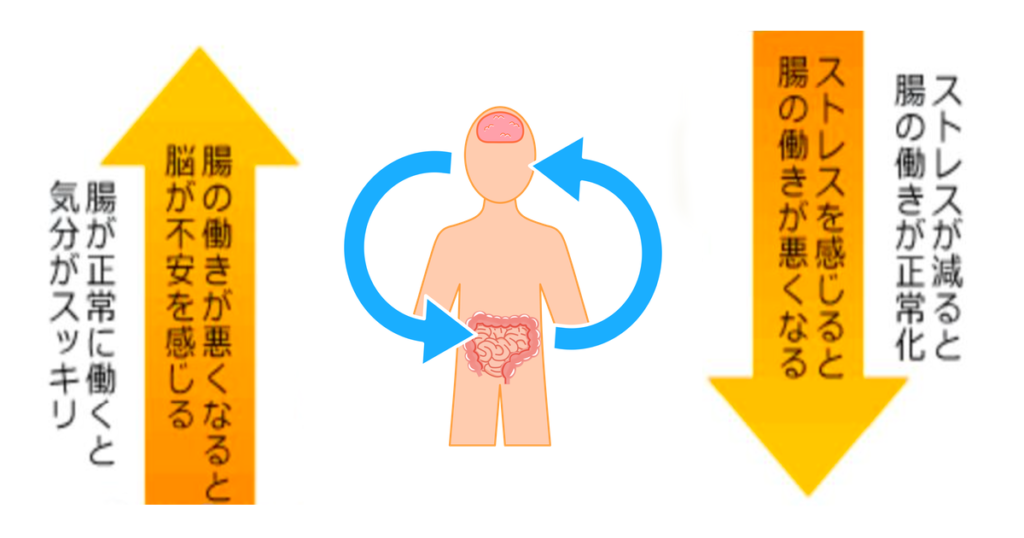

脳腸相関

脳腸相関とは、ストレスを共有し合っていて、密接に影響を及ぼしあうことを示します。例えば人間では、ストレスを感じるとお腹が痛くなり、便意をもよおしたりもます。これは脳が自律神経を介して、腸にストレスの刺激を伝えるからです。逆に腸に病原菌が感染すると、脳で不安感が増すといわれます。

脳と腸が迷走神経を通して、双方向のネットワークを作っている

・例えば腸内に不調があればその信号が自律神経を通して心臓に伝えられる

・心拍数を上げ下げして、腸の動きと連動して血流をコントロールしている

・まじめで神経質な人ほど腸にトラブルが多い傾向がある(交感神経、ストレス)

・自閉症スペクトラム、ADHDにも相関が…

脳と腸はとても強いつながりがあります。腸の調子が良くなれば、気分もスッキリします。